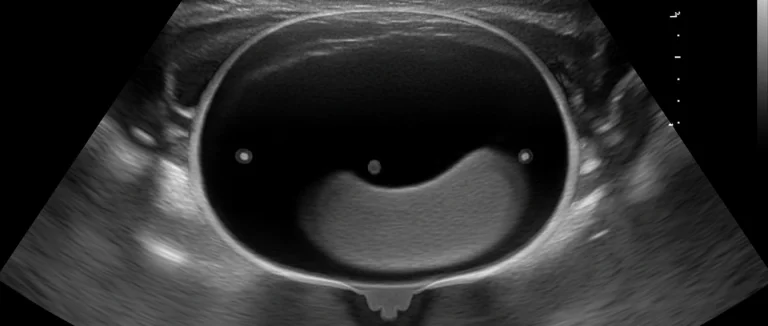

У мужчин анатомические особенности, такие как более длинная уретра, обычно снижают частоту УИ, однако наличие простатита или обструкций может стать причиной повторных инфекций. При подозрении на анатомическую предрасположенность рекомендуется пройти УЗИ почек и мочевого пузыря.

- УЗИ почек и мочевого пузыря – выявляет камни, обструкции и аномалии.

Анатомия играет ключевую роль в предрасположенности к УИ. У женщин уретра короче (около 4 см), что позволяет бактериям из кишечника быстро попасть в мочевой пузырь, особенно после половых контактов. У мужчин уретра длиннее (около 20 см), что создает естественный барьер, однако наличие простатита, урологических обструкций или камней в мочевом тракте может стать причиной рецидивов. У пациентов с анатомическими аномалиями, такими как укороченный уретральный канал или стриктуры, рекомендуется ультразвуковое исследование и иногда эндоскопическое обследование для выявления предрасположенности к инфекциям.

Для точного выявления причин рецидивов применяют несколько диагностических методов. Общий анализ мочи и посев позволяют определить тип бактерий и их чувствительность к антибиотикам, что критично для подбора терапии. УЗИ почек и мочевого пузыря визуализирует камни, обструкции и анатомические аномалии, которые могут служить резервуарами для бактерий. При подозрении на осложнённые формы, такие как абсцессы или пиелонефрит, используют компьютерную томографию (КТ) или магнитно-резонансную томографию (МРТ) для детального обследования. Дополнительные лабораторные исследования, включая уровень глюкозы в крови и гормональный профиль, помогают выявить сопутствующие заболевания, влияющие на иммунитет и микрофлору.